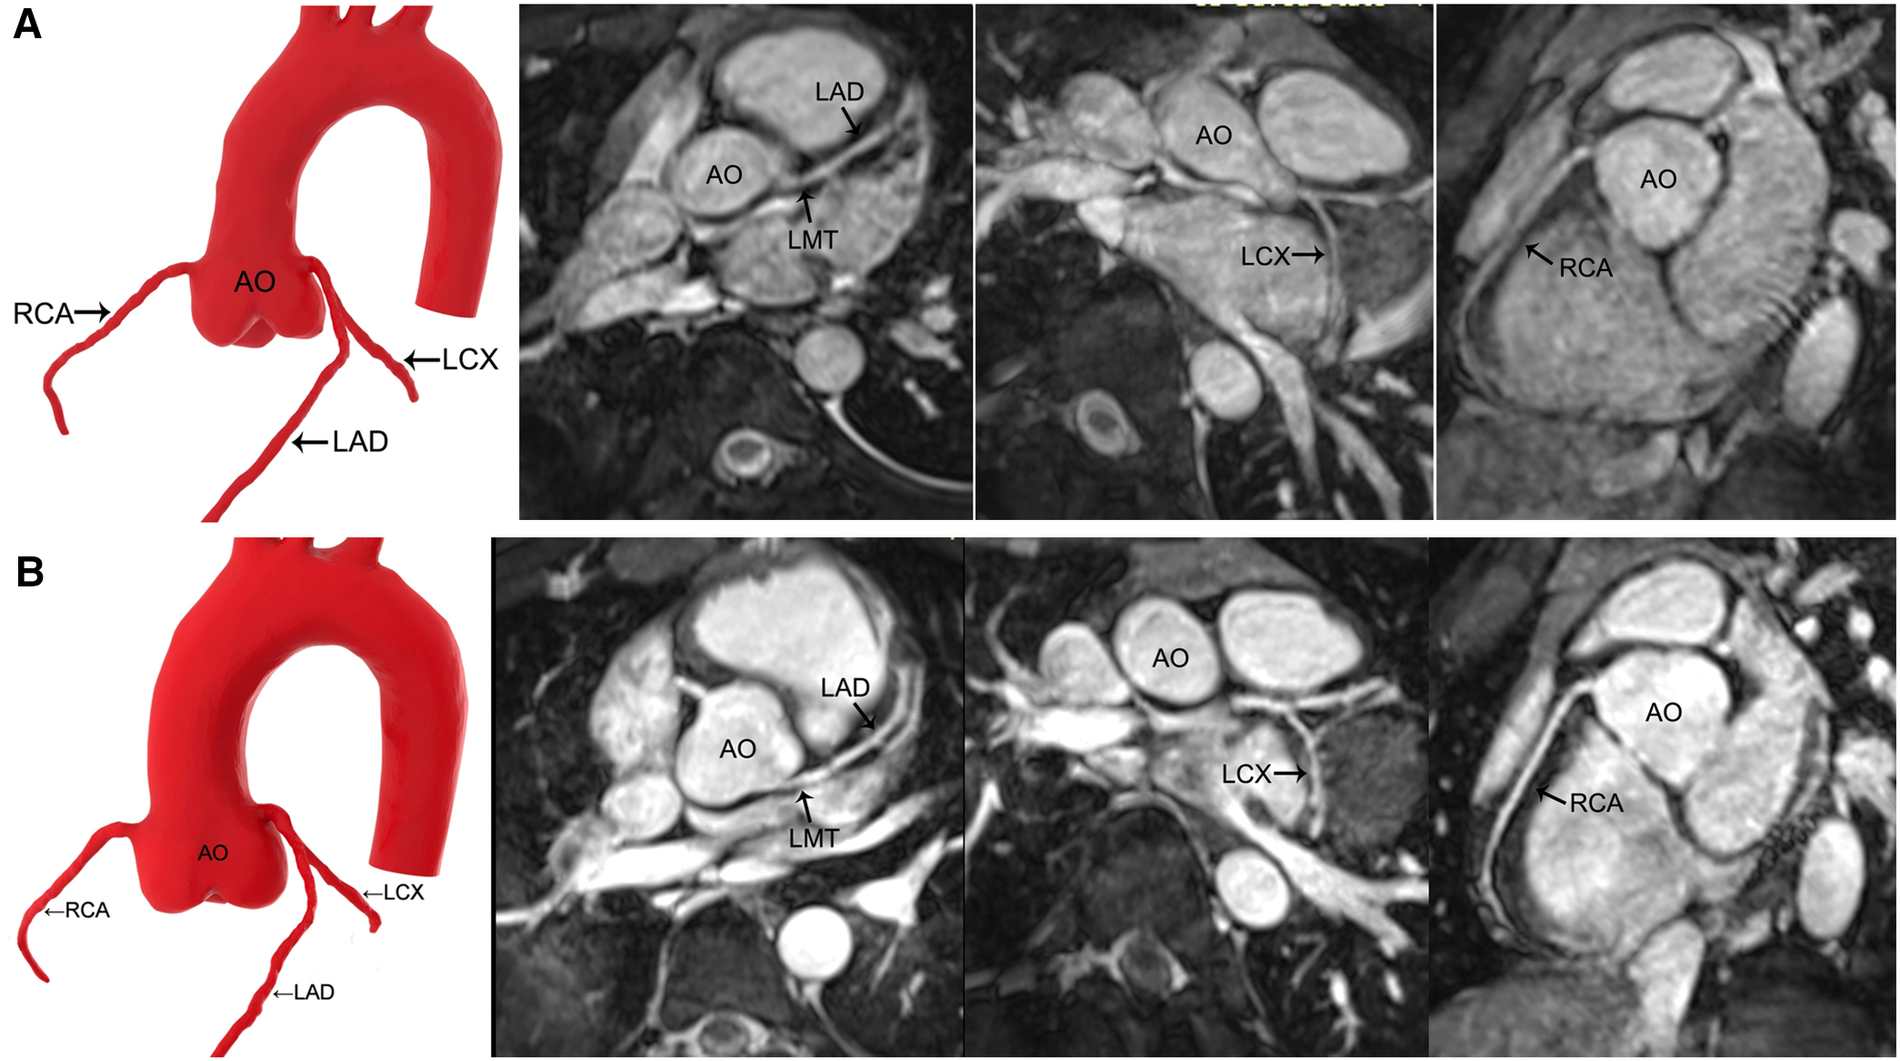

Figure 3

MR coronary angiography in a 13-year-old boy. (A) Precontrast imaging. (B) Postcontrast imaging. Despite an increase in the signal-to-noise ratio and contrast-to-noise ratio in the coronary arteries after the application of gadolinium-DTPA, contrast-enhanced MR coronary angiography neither improves the image quality significantly nor shows more side branches. AO, aorta; LMT, left main trunk; LAD, left anterior descending coronary artery; LCX, left circumflex coronary artery; RCA, right coronary artery.

The SNR and CNR of all the vessels in group 1 and group 2 and the LCX and RCA in group 3 improved after contrast agent injection (P < 0.05), whereas LMT and LAD remained unchanged in group 3 (P > 0.05) (Tables 4, 5) (Figures 2, 3).